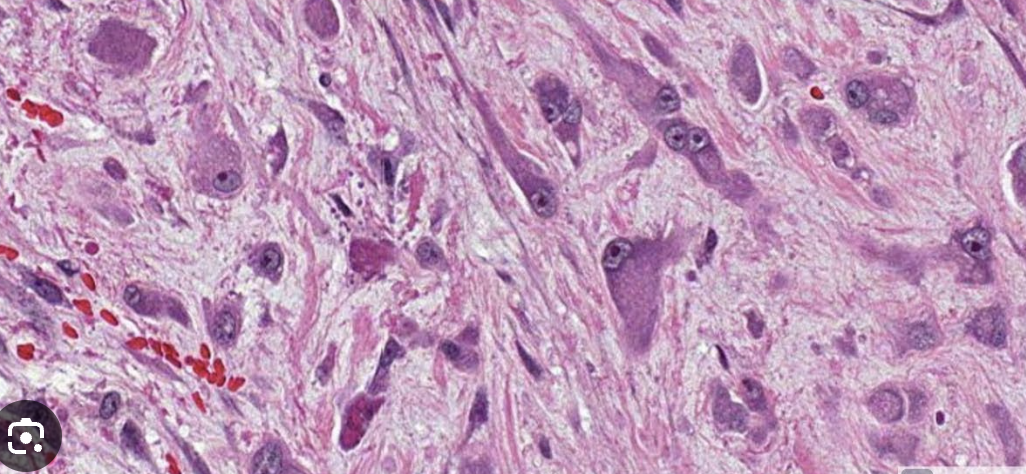

1) alveolar soft part sarcoma

2)

fibrous septeae

Alveolar pattern

Eosinophilic cytoplasm

Pleomorphic nuclei, prominent nucleoli, rhabdoid/plasmacytoid aspect

3) t(X;17) = ASPRCR1-TFE3

4) metastatic renal cell carcinoma